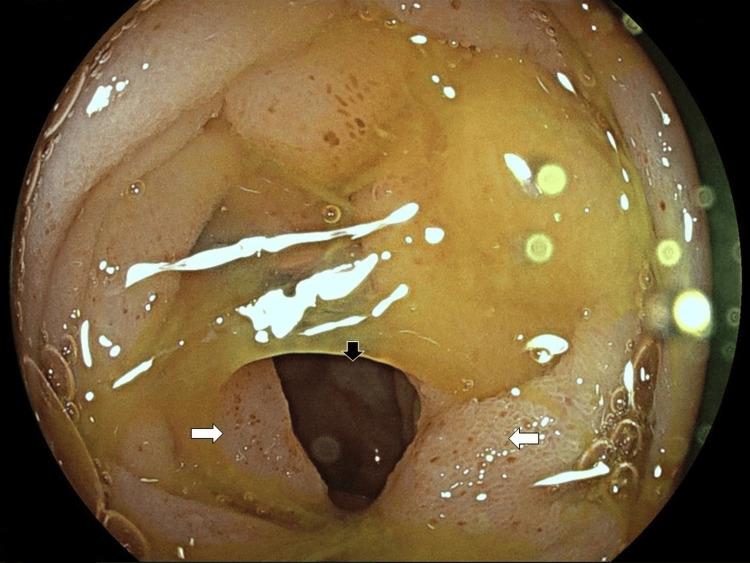

Cocaine represents one of the most frequently used recreational drugs worldwide. Cocaine-related disorders mostly affect the nervous and cardiovascular system, although gastrointestinal complications are not negligible and sometimes life-threatening. The most common gastrointestinal manifestations of cocaine abuse are ulceration, infarction, perforation, ischemic enterocolitis, and rarely hemorrhage, with mesenteric ischemia being the underlying pathophysiological mechanism. Herein, we report a rare case of cocaine-induced small bowel obstruction in a young female patient, caused by chronic mesenteric ischemia and excessive intestinal wall fibrosis.

可卡因是全球最常用的消遣性毒品之一。与可卡因相关的疾病主要影响神经和心血管系统,尽管胃肠道并发症也不容忽视,有时甚至会危及生命。可卡因滥用最常见的胃肠道表现是溃疡、梗死、穿孔、缺血性小肠结肠炎,很少有出血情况,肠系膜缺血是潜在的病理生理机制。在此,我们报告一例年轻女性患者罕见的可卡因诱发的小肠梗阻病例,其病因是慢性肠系膜缺血和肠壁过度纤维化。